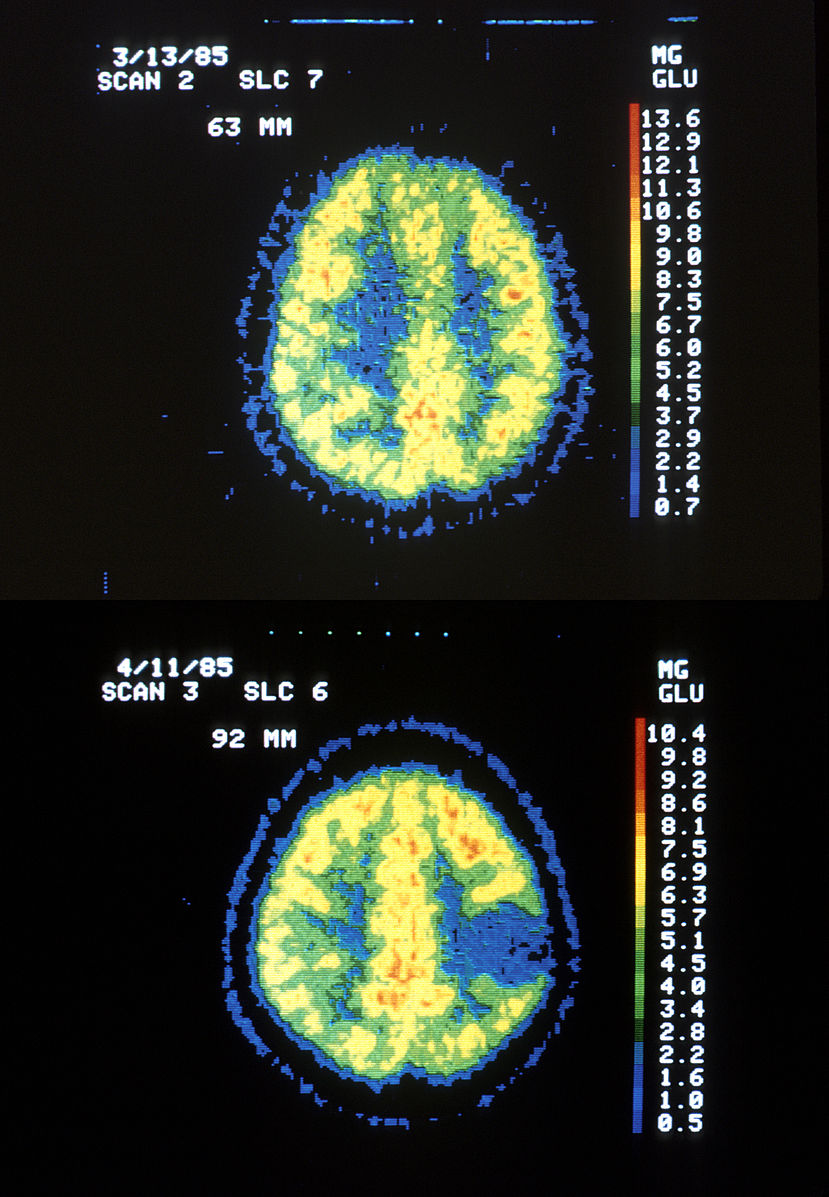

- Increased Intracranial Pressure (Cushing’s Triad, Blown (fixed, dilated) Pupil, Papilledema, Ptosis, Loss of consciousness, Otorrhea, Rhinorrhea), Craniotomy, Lumbar Punction (CSF – pink/cloudy/abnormal proteins), Manometer, EEG, MRI, CT scan, PET scan, Doppler ultrasound